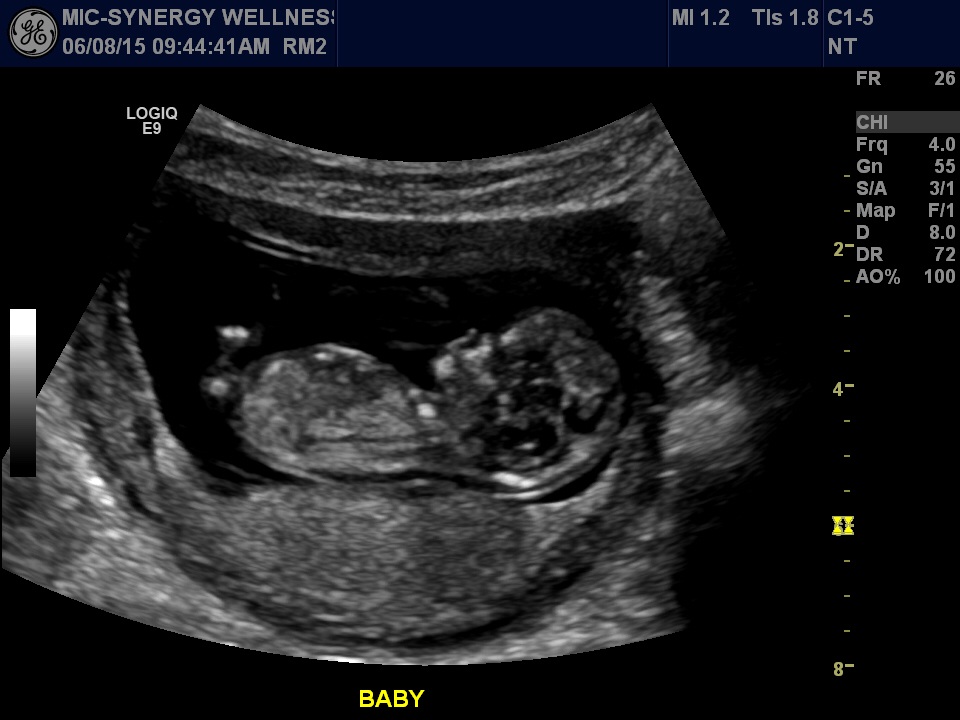

Had our second ultrasound baby was super active and was sucking its thumb ! Heartbeat was 156 Bpm.Ultrasound taken at 12 wks 4 days and today I'm 13 weeks ! Does anyone have a gender guess for my little nugget ? ❤️